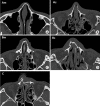

Methods: The subjects were patients who underwent closed reduction under general anesthesia from January 2017 to December 2018. Based on the modified Murray classification, patients were classified into five groups according to the fracture site, septal fracture, and deviation. A total of 211 patients were sent a web-based survey on postoperative satisfaction and complications, as well as intention for revision and cosmetic surgery. Sixty-one patients (28.9%) responded.

Results: There were no significant differences in aesthetic and functional satisfaction or satisfaction with closed reduction according to the fracture type, site, or severity. Postoperative functional complications developed in 14 of 61 patients (22.95%). With 10 out of 24 (41.67%) patients (p = 0.044), the bilateral fracture with septal fracture or prominent septal deviation type had a higher incidence of complications than the other types.